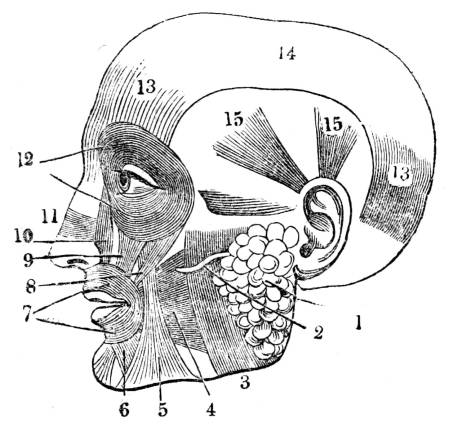

Fig. CXXXIV.—

View of the Respiratory Apparatus in

Man.

1. The Trachea. 2. The right lung. 3. The left lung.

4. Fissures, dividing each lung into, 5. Large portions

termed lobes. 6. Smaller divisions termed lobules. 7.

Pericardium. 8. Heart. 9. Aorta. 10. Diaphragm separating

the cavity of the thorax from that of the abdomen.